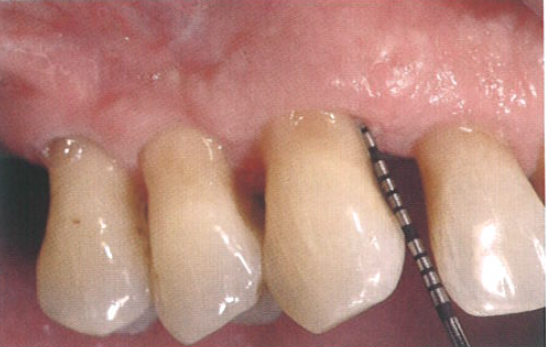

在为期15年的牙周维护治疗期间,由于患者的疏忽偶尔没有按时复诊,就诊时观察到牙周炎症的复发。图1显示探诊深度为7 mm,并伴有探诊出血。

图1  患者的牙周探诊深度为7 mm,且伴有探诊出血